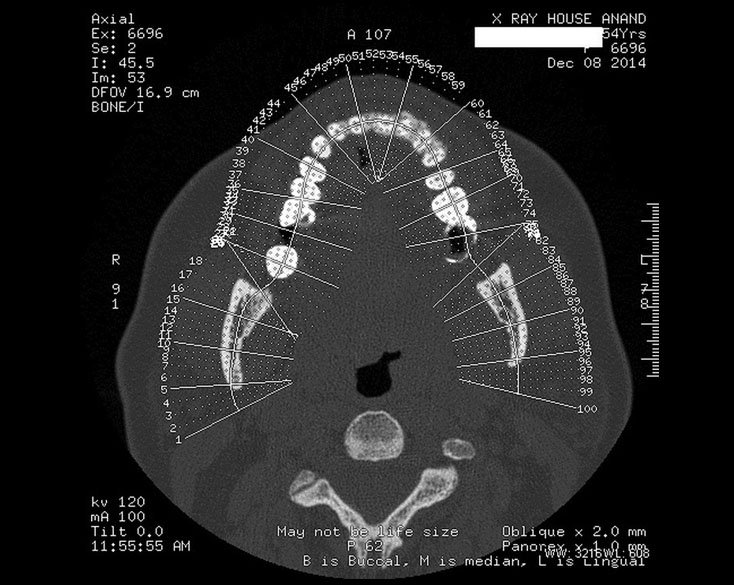

DENTAL CTSCAN